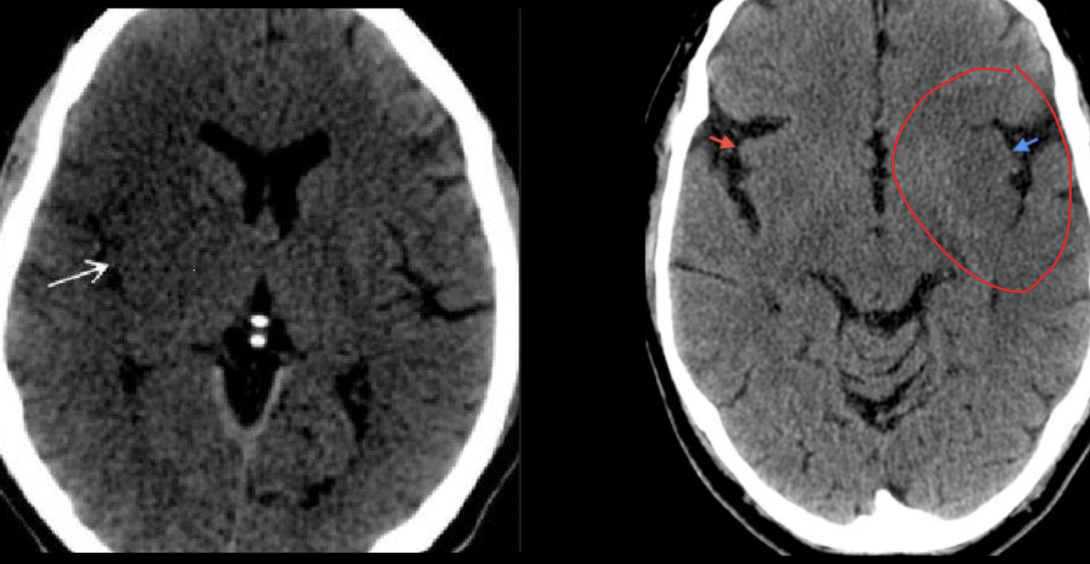

16

Diagnóstico:

A

EVC isquémico en fase aguda

18

EVC isquémico en fase a subaguda (24 a 72 h)

Características de la fase aguda del EVC isquémico

De 7 a 24hrs

Edema, borramiento de giros y efecto de masa

Características del EVC isquémico en fase subaguda

De 24 a 72hrs

Menos edema pero mucha hipodensidad